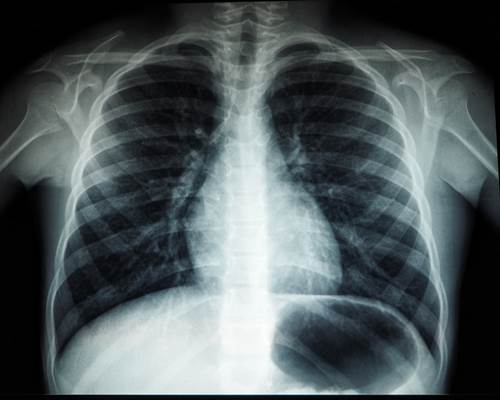

Диагностика болезней легких и бронхов с помощью рентген-аппарата

Первое назначение при подозрении на патологию дыхательных органов — рентгенография. Обследование проводят в 2-х проекциях: фас и профиль. Рентген-процедура помог...